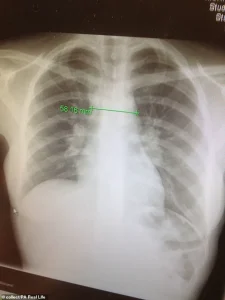

Hearing the words, stage 4 Hodgkin lymphoma (a cancer that starts in the lymph) felt unreal.

Surgery wasn’t an option, so within days I was started on six months of chemotherapy followed by a month of radiotherapy at the Royal Marsden Hospital in London.